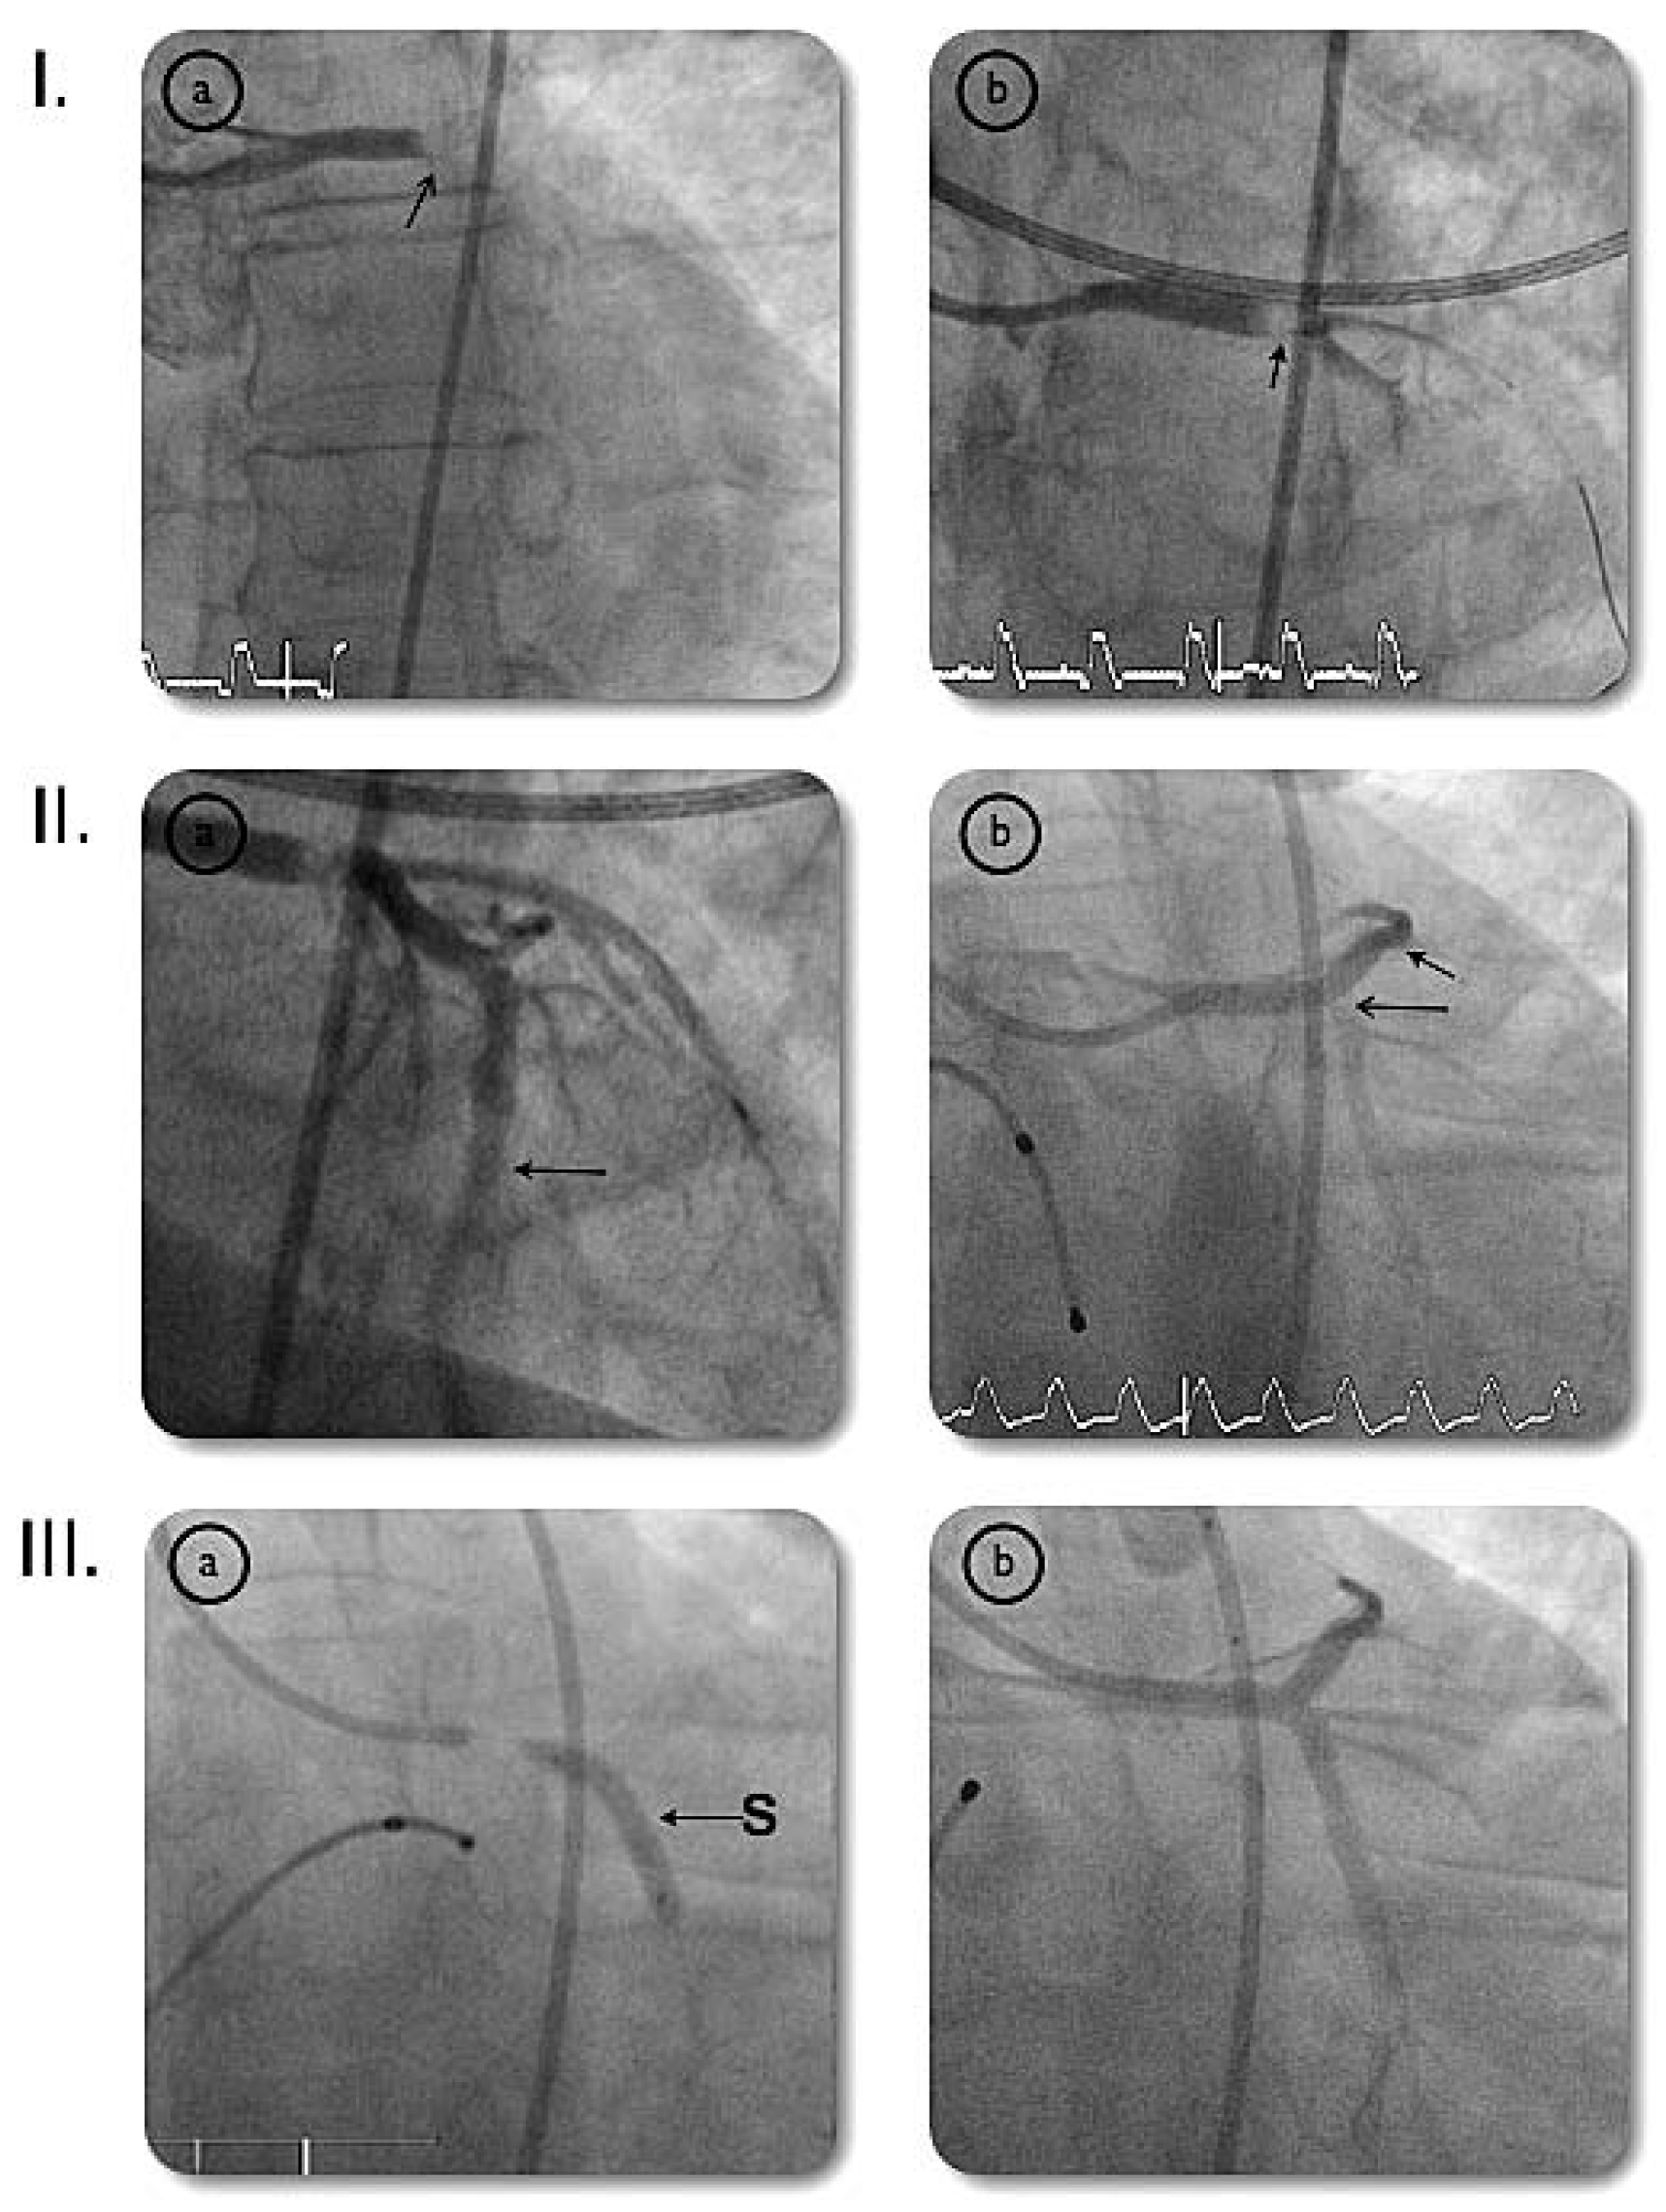

Very Late Stent Thrombosis of a Paclitaxel-Eluting Stent After Left Main Coronary Artery Stenting

Case report